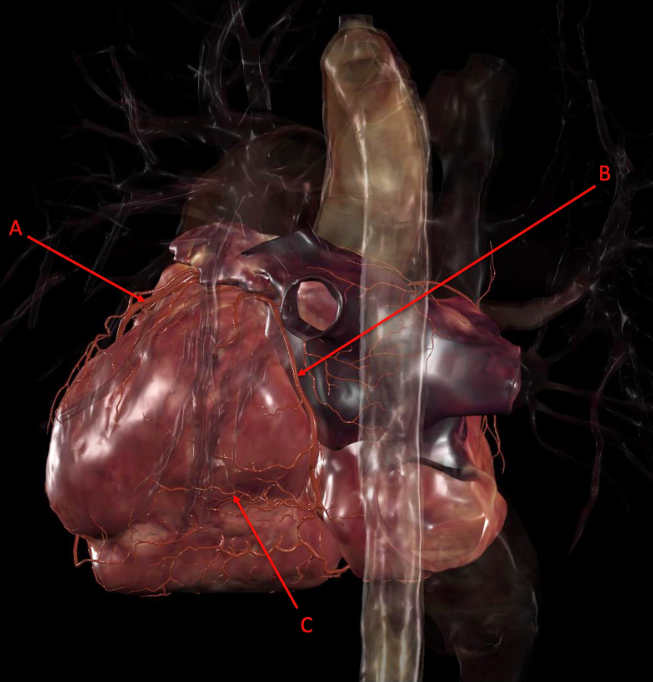

A. sinoatrial node

B. atrioventricular node

C. bundle of His